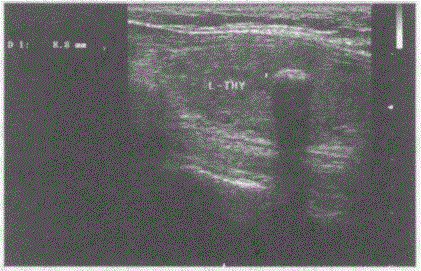

问题 临床资料:男,48岁,常规体检。 超声综合描述:甲状腺左叶可见直径0.9cm弧形强回声光带,后伴声影。 超声提示:

选项 A.甲状腺异物(左叶) B.甲状腺结石(左叶) C.甲状腺钙化灶(左叶) D.慢性淋巴细胞性甲状腺炎(桥本氏病)

答案 C